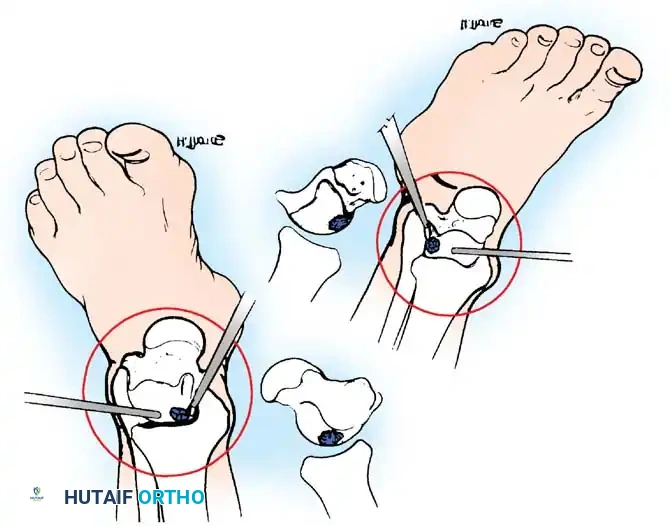

Fig. 42-48 Anterolateral (A) and anteromedial (B) portals for arthroscopic excision of osteochondritis dissecans of ankle. (Redrawn from Parisien JS: Diagnostic and surgical arthroscopy of the ankle: technique and indications, Bull Hosp Jt Dis 45:38, 1985.)

- Anteromedial Portal: Established first. Located just medial to the tibialis anterior tendon at the level of the joint line. A #11 blade is used to incise the skin only. A mosquito hemostat is used for blunt dissection down to the capsule to avoid injury to the saphenous vein and nerve.

- Anterolateral Portal: Established under direct intra-articular visualization. Located just lateral to the peroneus tertius tendon. Transillumination from the arthroscope helps identify and avoid the SPN branches.

Fig. 42-49 Arthroscopic drilling of osteochondritis dissecans of talus. Single Kirschner wire through hole drilled in malleolus produces multiple holes in crater of talus when ankle is flexed at different degrees. (Redrawn from Guhl JF: New techniques for arthroscopic surgery of the ankle: preliminary report, Orthopedics 9:261, 1986.)

Step-by-Step Transmalleolar Drilling:

1. Targeting: An anterior cruciate ligament (ACL) or specialized ankle drill guide is introduced through the arthroscopic portal and placed precisely over the center of the talar defect.

2. Incision: A small stab incision is made over the medial or lateral malleolus, depending on the lesion's location.

3. Drilling: A 1.6-mm or 2.0-mm Kirschner wire (K-wire) is drilled through the malleolus, across the joint space, and into the talar defect.

4. Maximizing Perforations: Multiple holes can be drilled in the crater in the talus through one single hole drilled through the malleolus. This is achieved by keeping the K-wire trajectory constant while combining dorsiflexion and plantarflexion of the ankle (as illustrated in Fig. 42-49). This technique minimizes iatrogenic damage to the malleolar articular surface while maximizing the surface area of marrow stimulation within the talar defect.

5. Depth: The K-wire should penetrate approximately 10 to 15 mm into the subchondral bone to ensure adequate access to vascular marrow.